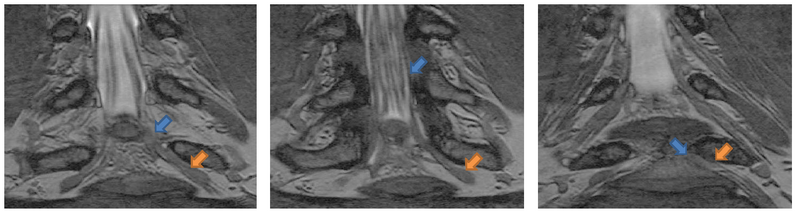

We show below a qualitative comparison between manual left atrium segmentations (first row) and automatic segmentations produced by our approach (second row).

Qualitative evaluation of left atrium segmentations in three different sub- jects. First row shows expert manual segmentations. The corresponding automatic segmentations produced by our method are in the second row.